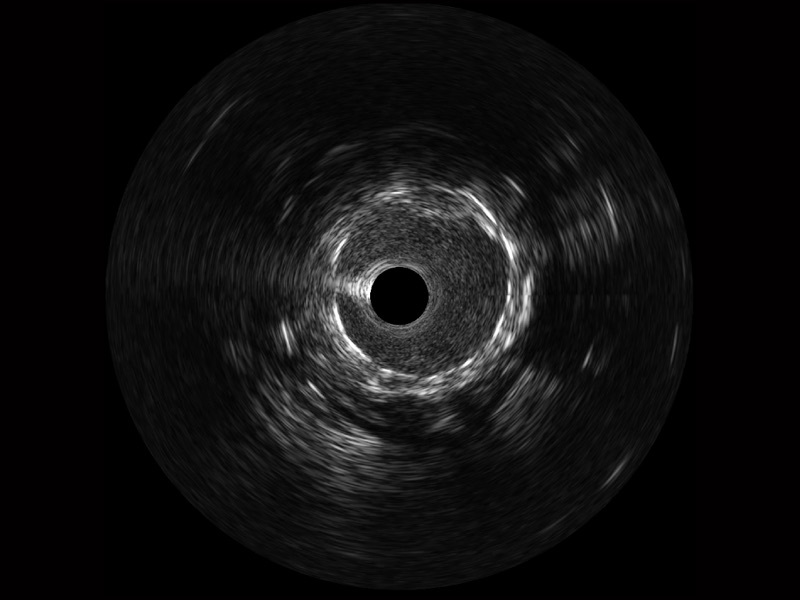

• 银河集团官网宽频IVUS图像

• 传统IVUS图像

对比传统IVUS导管成像,银河集团官网宽频IVUS图像的近场支架梁显影更细腻,远场中膜外血管仍清晰可辨,兼顾远中近,兼顾分辨力与穿透深度